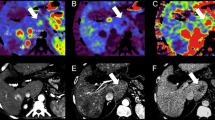

Focus of HCC within a dysplastic nodule in a 63-year-old man. a Unenhanced breath-hold T1-weighted fast low-angle-shot MR image (TR/TE: 153 ms/4 ms) shows hyperintense nodule (arrows). b Gd-DTPA-enhanced hepatic arterial-phase MR image shows subtle enhancement with two prominent nodules (arrows). c SPIO-enhanced T2*-weighted fast image with steady precession MR image (TR/TE: 150 ms/13 ms) shows two high-signal nodules (arrows). The SPIO is taken up by the dysplastic nodule but not by the focus of HCC. d Computed tomography during arterial portography shows round well-defined area of portal perfusion defect (arrows). e Computed tomography during hepatic arteriography shows a small discrete area of high attenuation (arrow). Note the small discrete area of CT hepatic arteriography, corresponding to an area of high signal intensity on c SPIO-enhanced MR images; however, another nodule showed on SPIO-enhanced MR images is not detected

Several previous studies [13, 19] reported that gadolinium-enhanced MR images were significantly greater accuracy in the detection of small HCCs than SPIO-enhanced MR images; however, Krinsky et al. [21] evaluated the sensitivity of dynamic gadolinium-enhanced MR images in 71 patients who had late-stage cirrhosis and they identified only 55% of all HCC nodules. In our study, the sensitivity to detection of HCC on Gd-DTPA-enhanced dynamic MR images was similar to that of SPIO-enhanced MR images. We suspected that the sensitivity of Gd-DTPA enhanced MR images may have been low because of the hypovascular mass and the poor detection rate of small HCCs (<1 cm; Fig. 3).

A 56-year-old man with HCC in segment II. a Computed tomography during hepatic arteriography shows no abnormal finding of the liver. b Computed tomography during hepatic arteriography shows predominant enhancement in the dependent area of the liver; however, abnormal perfusion defect is not seen in the liver. Intense enhancement associated with laminar flow in the portal vein is seen at CT arterial portography (arrows). c SPIO-enhanced T2*-weighted fast image with steady precession MR image (TR/TE: 150 ms/13 ms) shows a well-defined homogeneous mass in segment II (arrows)